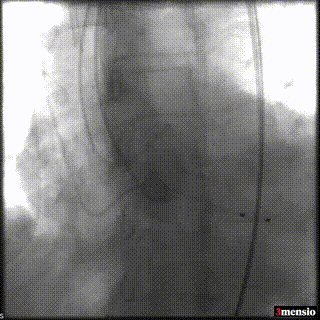

手术过程概览:

根部造影,可见明显反流,猪尾在右窦